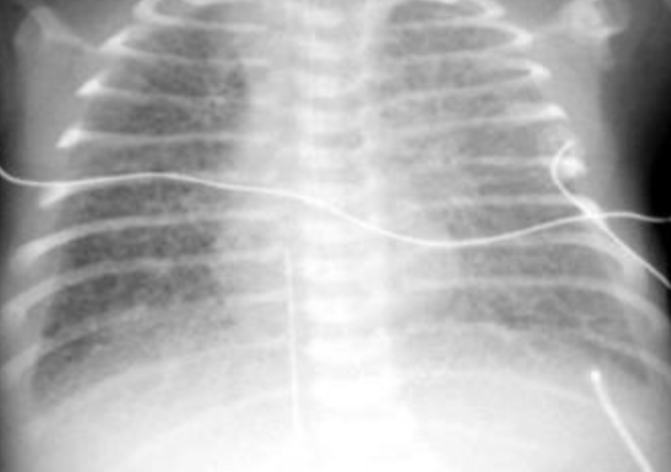

- AP chest film showing that the naso-gastric tube (NGT) is inside the left - (1 hemi-thorax. There is an ill-defined line separating the upper and middle .zones of left lung

- The diagnosis was ruptured left hemi-diaphragm possibly secondary to - (2 .the trauma to the abdomen

- During surgery, there was a ruptured diaphragm and intestines, spleen - (3 and stomach were found in the left chest. There was evidence of left sided .CDH which facilitated the rupture